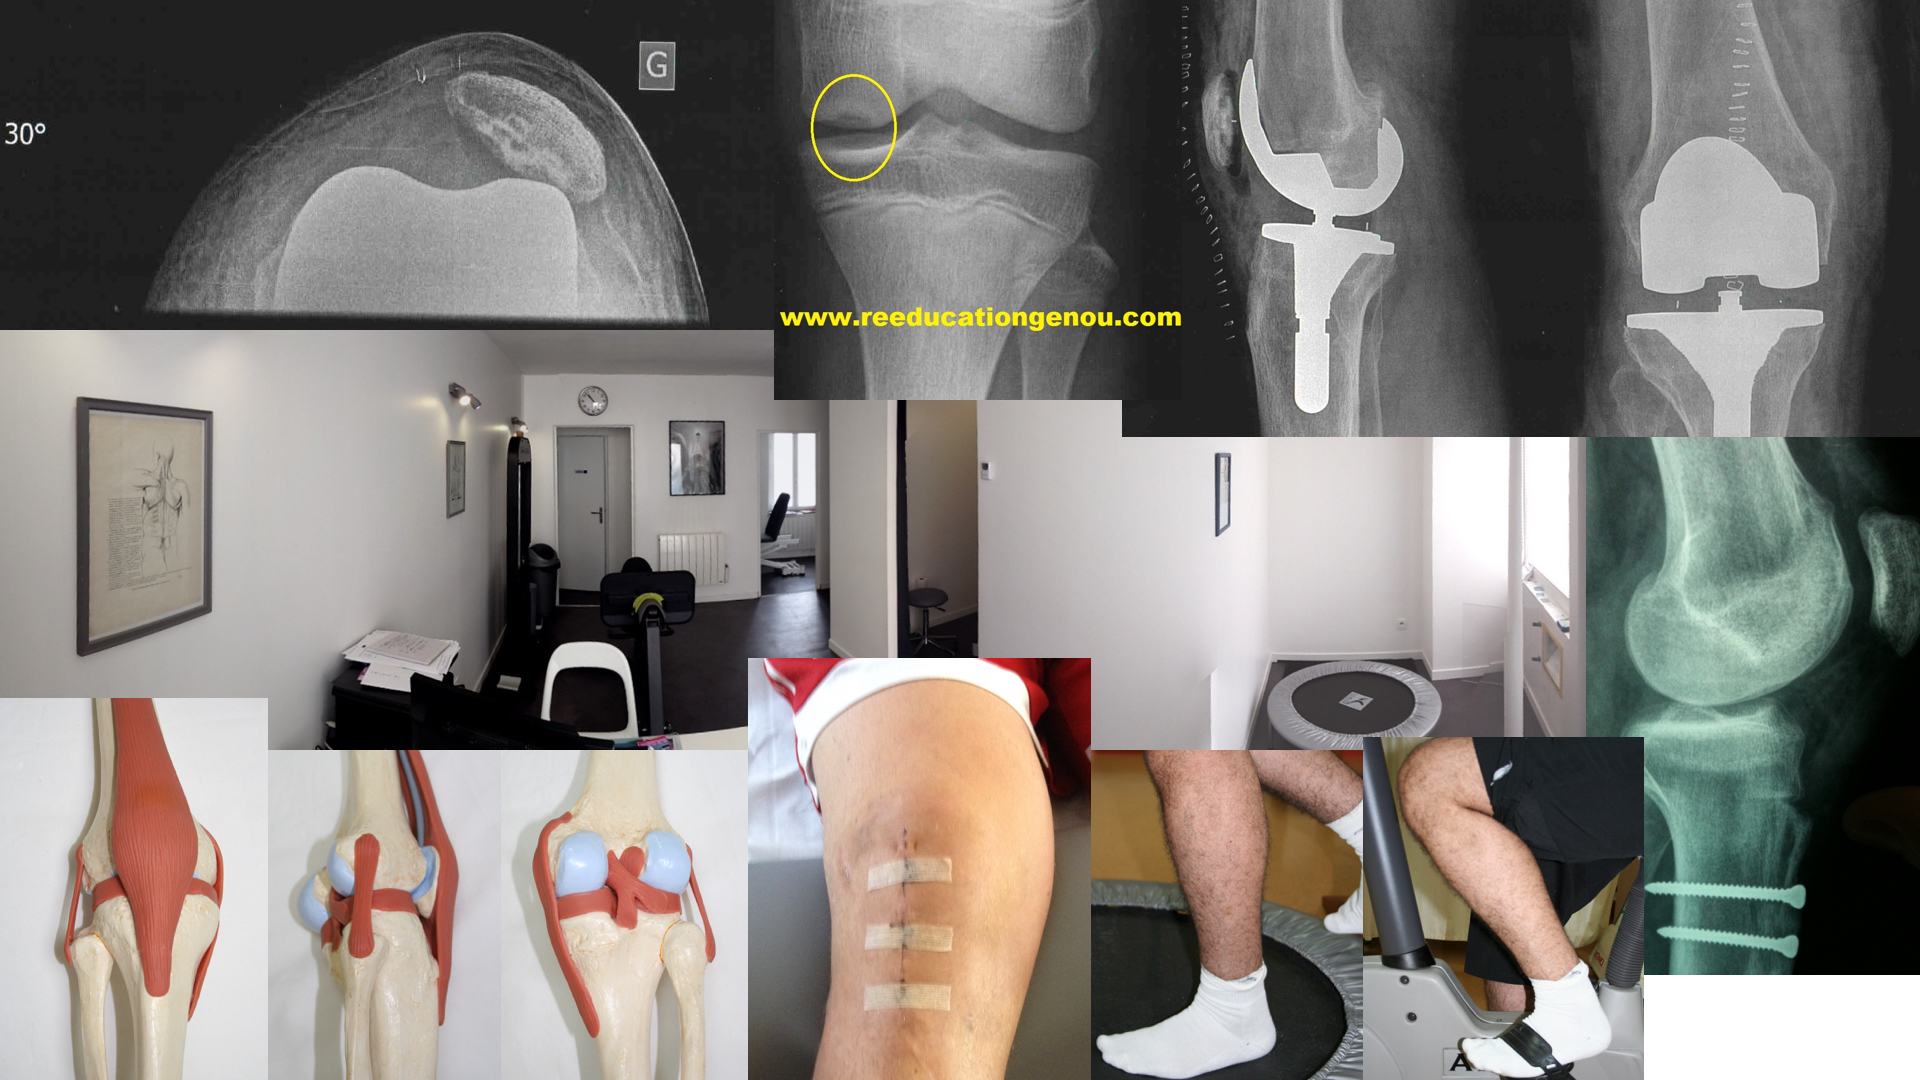

Après le 4ème mois : tests fonctionnels, retour sur terrain

La période de reprise sportive "cadrée" : du 4-5ème au 12ème mois voire 2 ans

c'est aussi la phase où l'on intensifie la préparation physique et la réathlétisation

chirurgicalement :

objectivement :

• ISOCINETISME si cabinet équipé

TOUS LES TESTS FONCTIONNELS DOIVENT ËTRE CORRECTEMENT EFFECTUES SOUS PEINE DE REBLESSURE